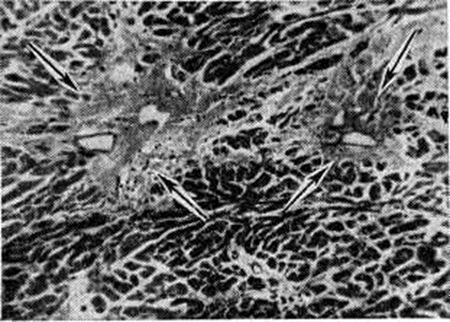

Рис. 2.

Характерные околососудистые рубчики в миокарде (указаны стрелками) после перенесённого ревматизма (окраска по Массону).

Миокардитический кардиосклероз — исход миокардитов (смотри полный свод знаний) инфекционно-аллергической, бактериальной или вирусной этиологии, сопровождающихся экссудативными и пролиферативными процессами в строме миокарда и деструктивными изменениями миоцитов. К этим процессам относится Кардиосклероз после перенесённого ревматизма, дифтерии, скарлатины, заражения Коксаки-вирусом или энцефаломиокардитическим вирусом, изредка вирусом полиомиелита или оспенной вакцинации; чрезвычайной редкостью является Кардиосклероз после туберкулёзного или сифилитического интерстициального миокардита. Миокардитический Кардиосклероз может носить характер диффузного миофиброза, локализующегося преимущественно в левом желудочке, и выражается в распространённом огрубении аргирофильной стромы миокарда и образовании коллагеновых волокон, что придаёт строме вид грубой решётки, в ячейках которой заключены отдельные мышечные волокна или группы их. Такой Кардиосклероз называют стромогенным. В случае же гибели небольших групп миоцитов возникают небольшие рубчики, или очажки Кардиосклероз. При диффузном ревматическом интерстициальном миокардите с мукоидной дезорганизацией стромы наблюдается диффузный интерстициальный миофиброз (цветной таблица, ст. 144, рисунок 3) и одновременно как исход ревматических гранулем около сосудов возникают овальные или звездчатые рубчики, являющиеся важным диагностическим признаком ревматизма (рисунок 2). Кардиосклероз (диффузный миофиброз) наблюдается также после аллергических миокардитов неясной этиологии (миокардита Фидлера, аллергического миокардита, описанного Я. Л. Рапопортом).